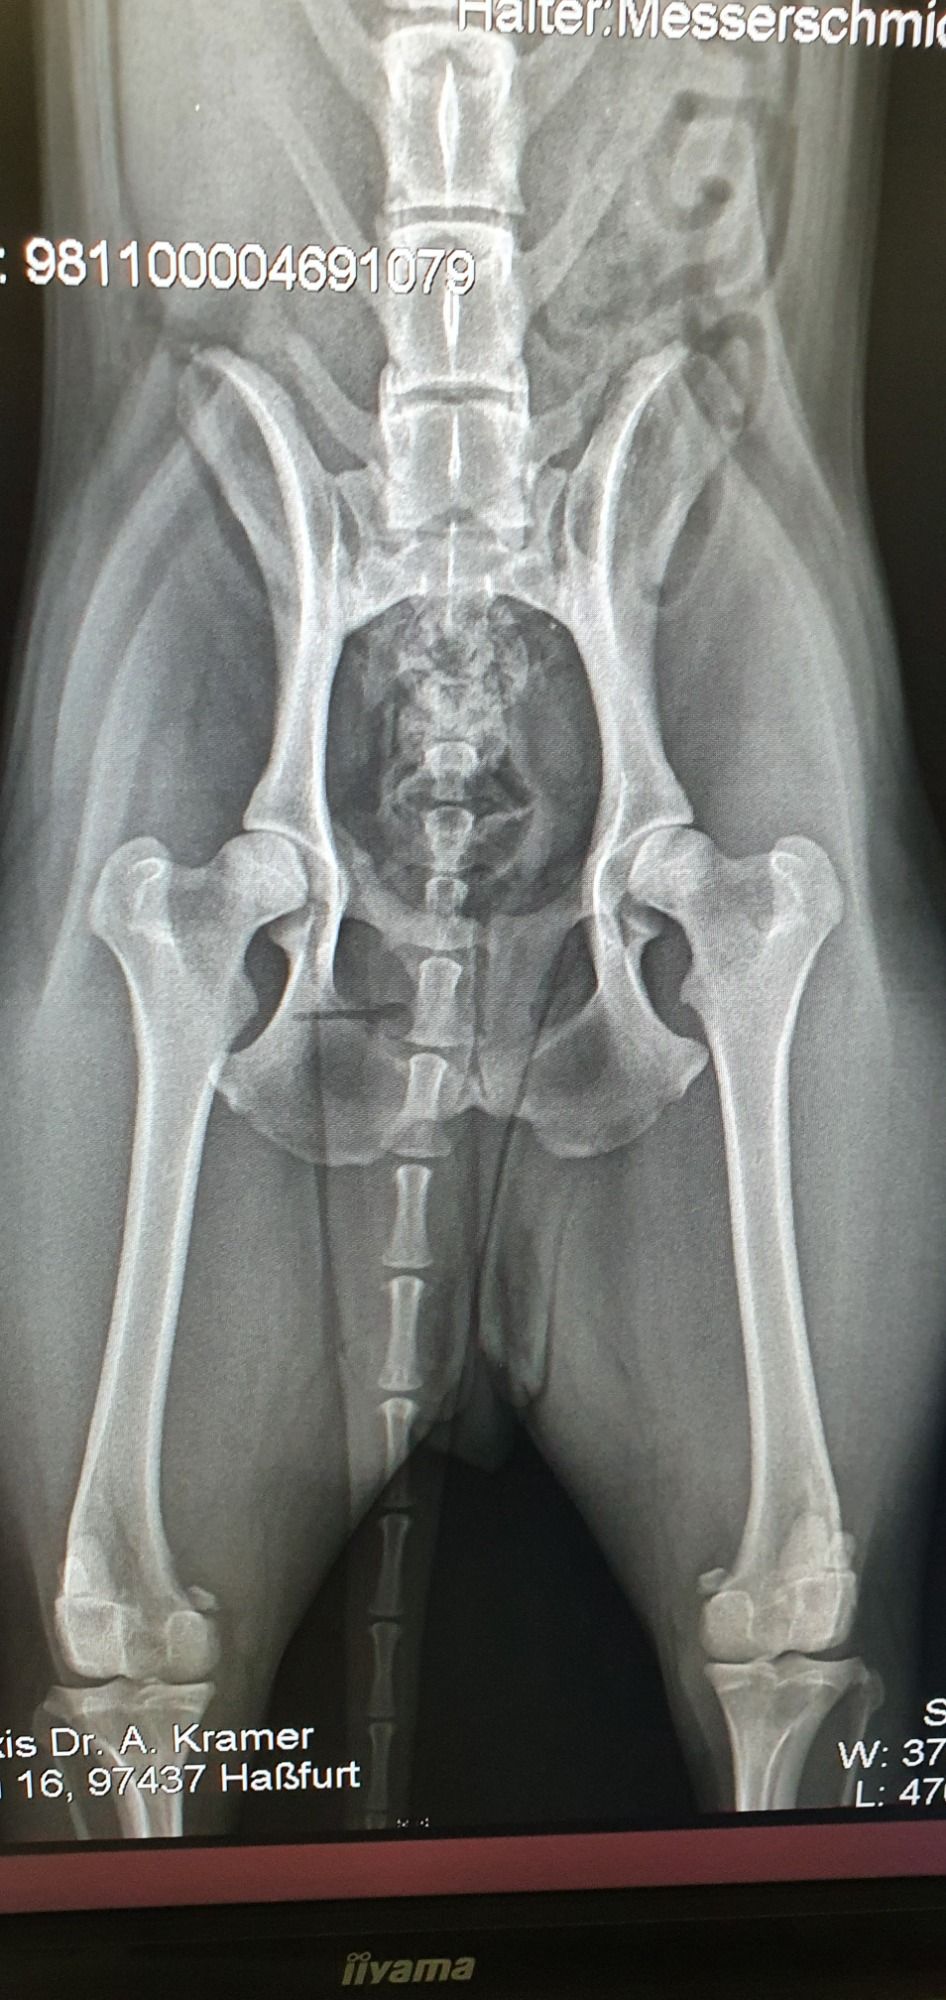

Striptease van Sapho´s Hoeve

*13.08.2019

Lightning VSH X Playfull VSH

Herz 0

HD B

Spondy 0